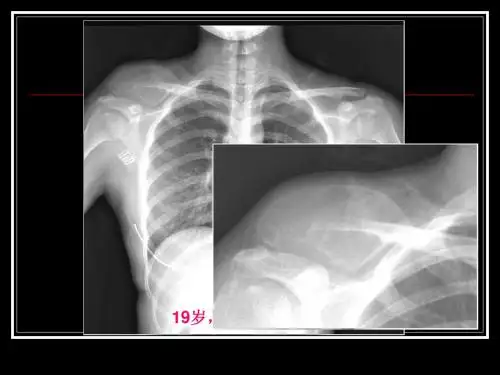

影像学表现ABC通常位于骨髓腔内,通过X线摄影、CT和MRI等成像技术可以观察到其典型表现。

X线摄影可以显示骨质变化,如骨质疏松和囊状改变。